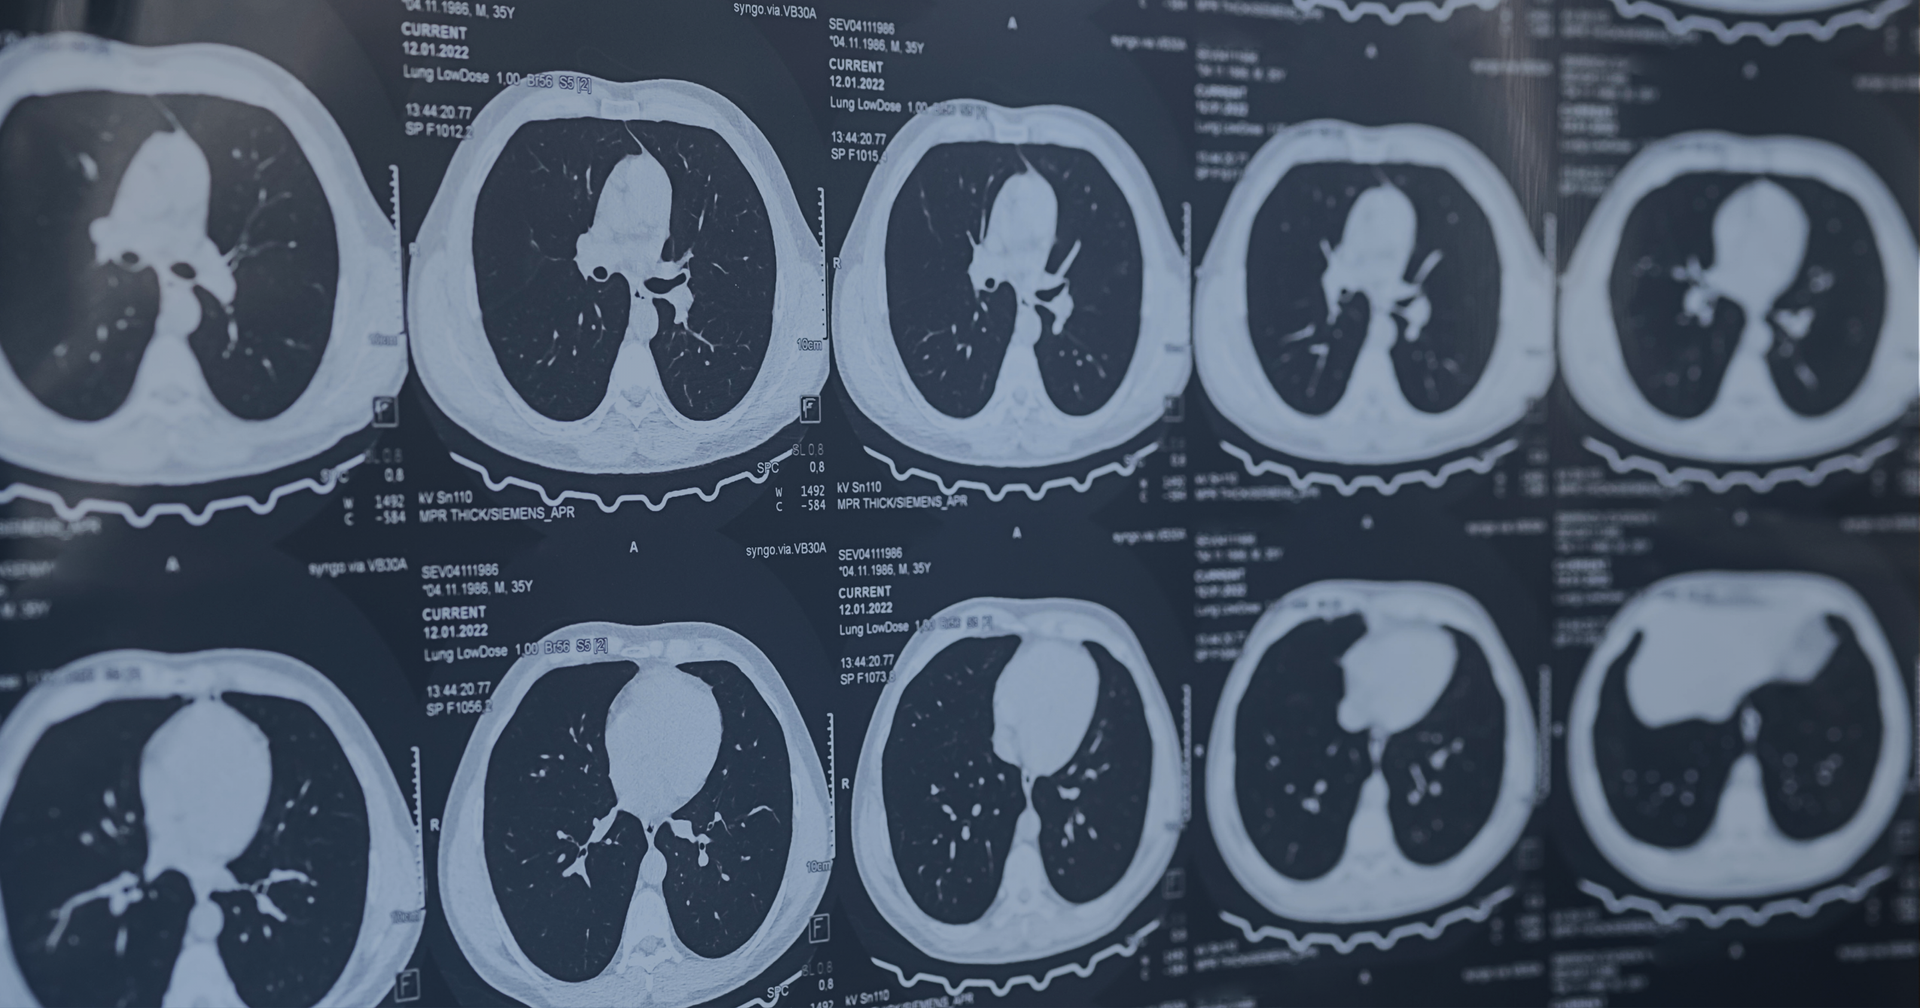

Our lung scans can detect lung cancers as well as various types of lung infections and lung diseases.

A computed tomography (CT) lung scan takes an extremely clear and accurate picture of the lungs and chest. One of the main benefits of these scans is the early detection of various lung cancers, which can be completely asymptomatic for months or even years.

A board-certified radiologist will review your lung scan and look for various signs of disease, including nodules, tumors, infections, and lesions.